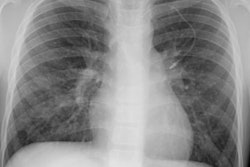

Intrathoracic lymphoproliferative disorders (LPDs) span a spectrum of benign lesions to those that are frankly malignant or have a malignant potential. The clonality of lymphoid populations is helpful in separating benign from malignant disorders. Polyclonality is usually reflective of benign disease, while monoclonality is usually indicative of malignancy. Stimulation of bronchus-associated lymphoid tissue (or BALT) and the Ebstein-Barr virus (EBV) are thought to play key roles in these disease processes. It has been postulated that the EBV genome may act as a stimulant, either as a primary or reactivated agent, particularly in disorders such as infectious mononucleosis and the post-transplant lymphoproliferative disorder.

Several generalizations have been made regarding the LPDs. These are: 1- older symptomatic patients have a more aggressive disease (i.e., lymphoma); 2- benign LPDs tend to be focal (i.e., lung or lymph nodes) and pleural effusions are rare in benign disease; and 3- the post-transplant LPDs may have a variety of radiographic findings (i.e., infiltrates, masses, and/or adenopathy). The site of disease may also provide a clue to the diagnosis. Parenchymal lung abnormalities are found in association with plasma cell granuloma (pulmonary pseudotumor), pseudolyphoma, and lymphatoid granulomatosis (angiocentric immunoproliferative lesion). While mediastinal disease suggests Castleman's disease, infectious mononucleosis, or angioimmunoblastic lymphadenopathy.